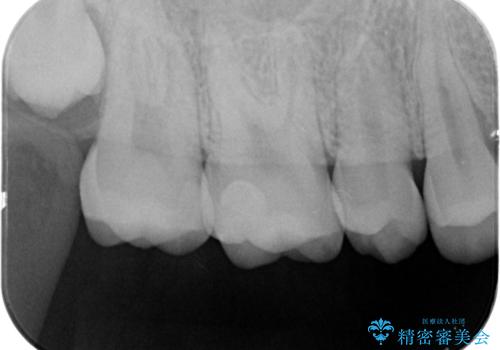

歯と歯の間の虫歯 e-maxインレーで修復

- 歯と歯の間に虫歯が見られたために、拡大鏡下でう蝕を取り除き、e-maxインレーで治療しました。

- e-maxインレー 7.7万円 費用は治療当時の料金となります